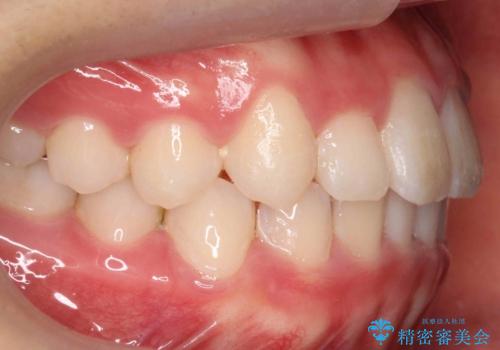

八重歯 歯を抜かずにインビザラインで

- 八重歯を主訴に来院。

抜かずに歯を少し削って入れる方法で並べました。

10代のうちに矯正をしておくと歯の移動は簡単で、歯ぐきも下がりにくいです。

可能なら低年齢のうちに矯正をするのがお勧めです。